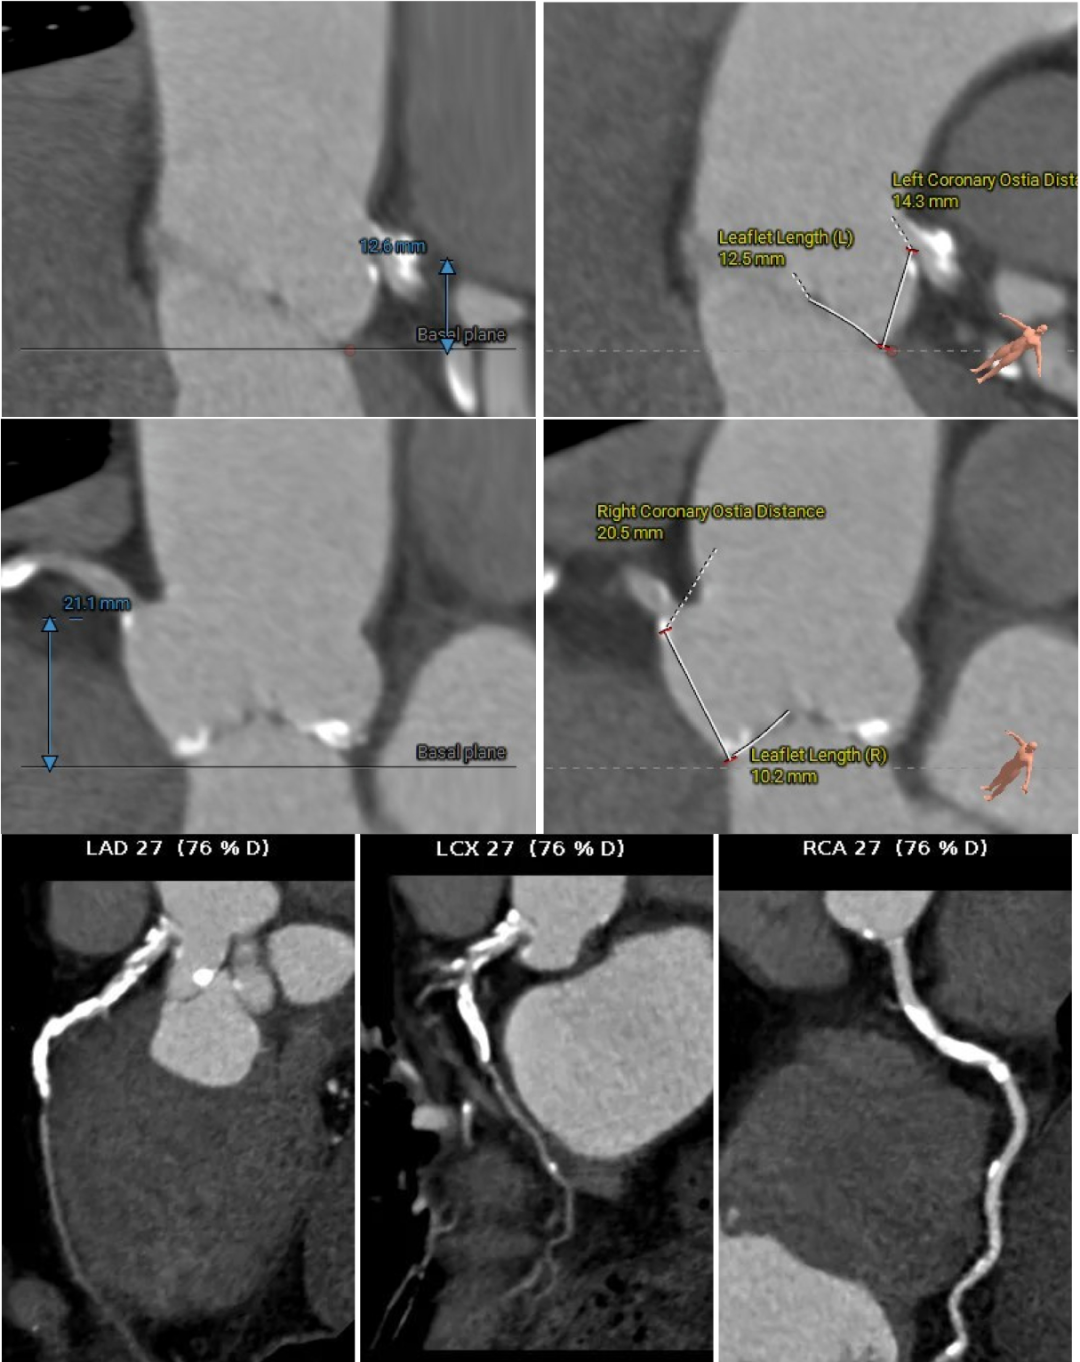

近日,昆山市中医医院心内科团队又成功为一名82岁高龄患者实施经导管主动脉瓣置换术。该患者主动脉瓣口面积仅0.2cm²,而正常成人主动脉瓣口面积一般约为3至4cm²。与此同时,患者还合并重度钙化的二叶式主动脉瓣、轻中度反流,左心室腔径偏小,并有帕金森病病史。多重高危因素叠加,意味着术中导丝跨瓣难度大,循环波动耐受差,整体风险很高。

术前评估越细,术中把握才越稳

进一步评估显示,患者瓣膜狭窄程度重,瓣叶钙化明显,左心室腔径偏小,手术中对器械通过、瓣膜释放以及循环稳定性的要求都更高。团队结合术前影像和整体身体状况,制定了周密的介入治疗方案,并做好相关风险预案。

CT评估

瓣膜评估